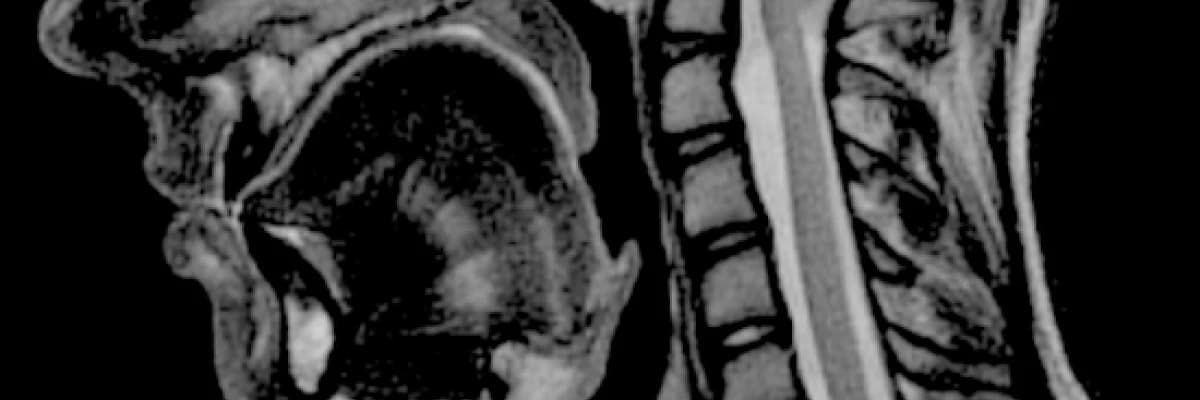

Hastamız 24 yaşında erkek. Yaklaşık 3 yıldır devam eden ense ağrısı, başdönmesi, kollarda uyuşma ve halsizlik hissi şikayetleri ile polikliniğimize başvurdu. Yapılan muaeyene ve radyolojik incelemeleri sonucu BEYİNCİK SARKMASI (Chiari Malformasyonu) tanısı koyduk. (Fotoğrafta görüldüğü gibi başın arka alt kısmındaki denge organı beyincik sarı ok yönünde omurilik kanalına doğru yaklaşık 2 cm inmişti. Normal seviyesi kesikli sarı çizgi hizasında olmalıydı). Beyincik omurilik kanalı içine doğru sarkmış ve burada sıkışmıştı. Hastaya ameliyat önerdik ve ameliyat ettik. Beyinciğin sarktığı bölge üzerindeki kafatası kemiğini, boyun kemiklerini ve beyin/omurilik zarını (dura) açarak omurilik ve beyinciği gevşettik. Pansumanları ve ilaç tedavilerini mütakip 2 gün sonra taburcu edildi.